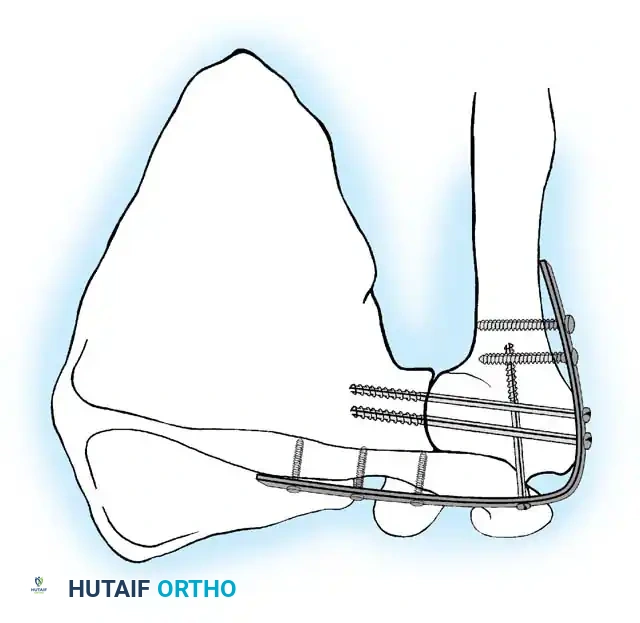

5. Rigid Internal Fixation

The most robust biomechanical construct involves a heavy, malleable plate (such as a 10- to 14-hole 4.5mm pelvic reconstruction plate or a dynamic compression plate). The plate is meticulously contoured to lie flat along the spine of the scapula, bend over the acromion, and extend down the lateral shaft of the humerus.

Screws are placed sequentially:

1. Scapular Spine: Cortical screws are placed into the dense bone of the scapular spine.

2. Acromiohumeral Fixation: Screws are passed through the plate, across the acromion, and into the humeral head.

3. Glenohumeral Fixation: Long, fully threaded cortical or cancellous screws are directed through the plate, through the humeral head, and deep into the glenoid neck and vault. This is the most critical step for achieving compression across the primary fusion site.

4. Humeral Shaft: The distal portion of the plate is secured to the humeral diaphysis.

If additional stability is required, or if bone quality is poor, a second plate (double plating technique) can be applied posteriorly.

Radiographic confirmation of a contoured reconstruction plate achieving rigid acromiohumeral and glenohumeral compression.